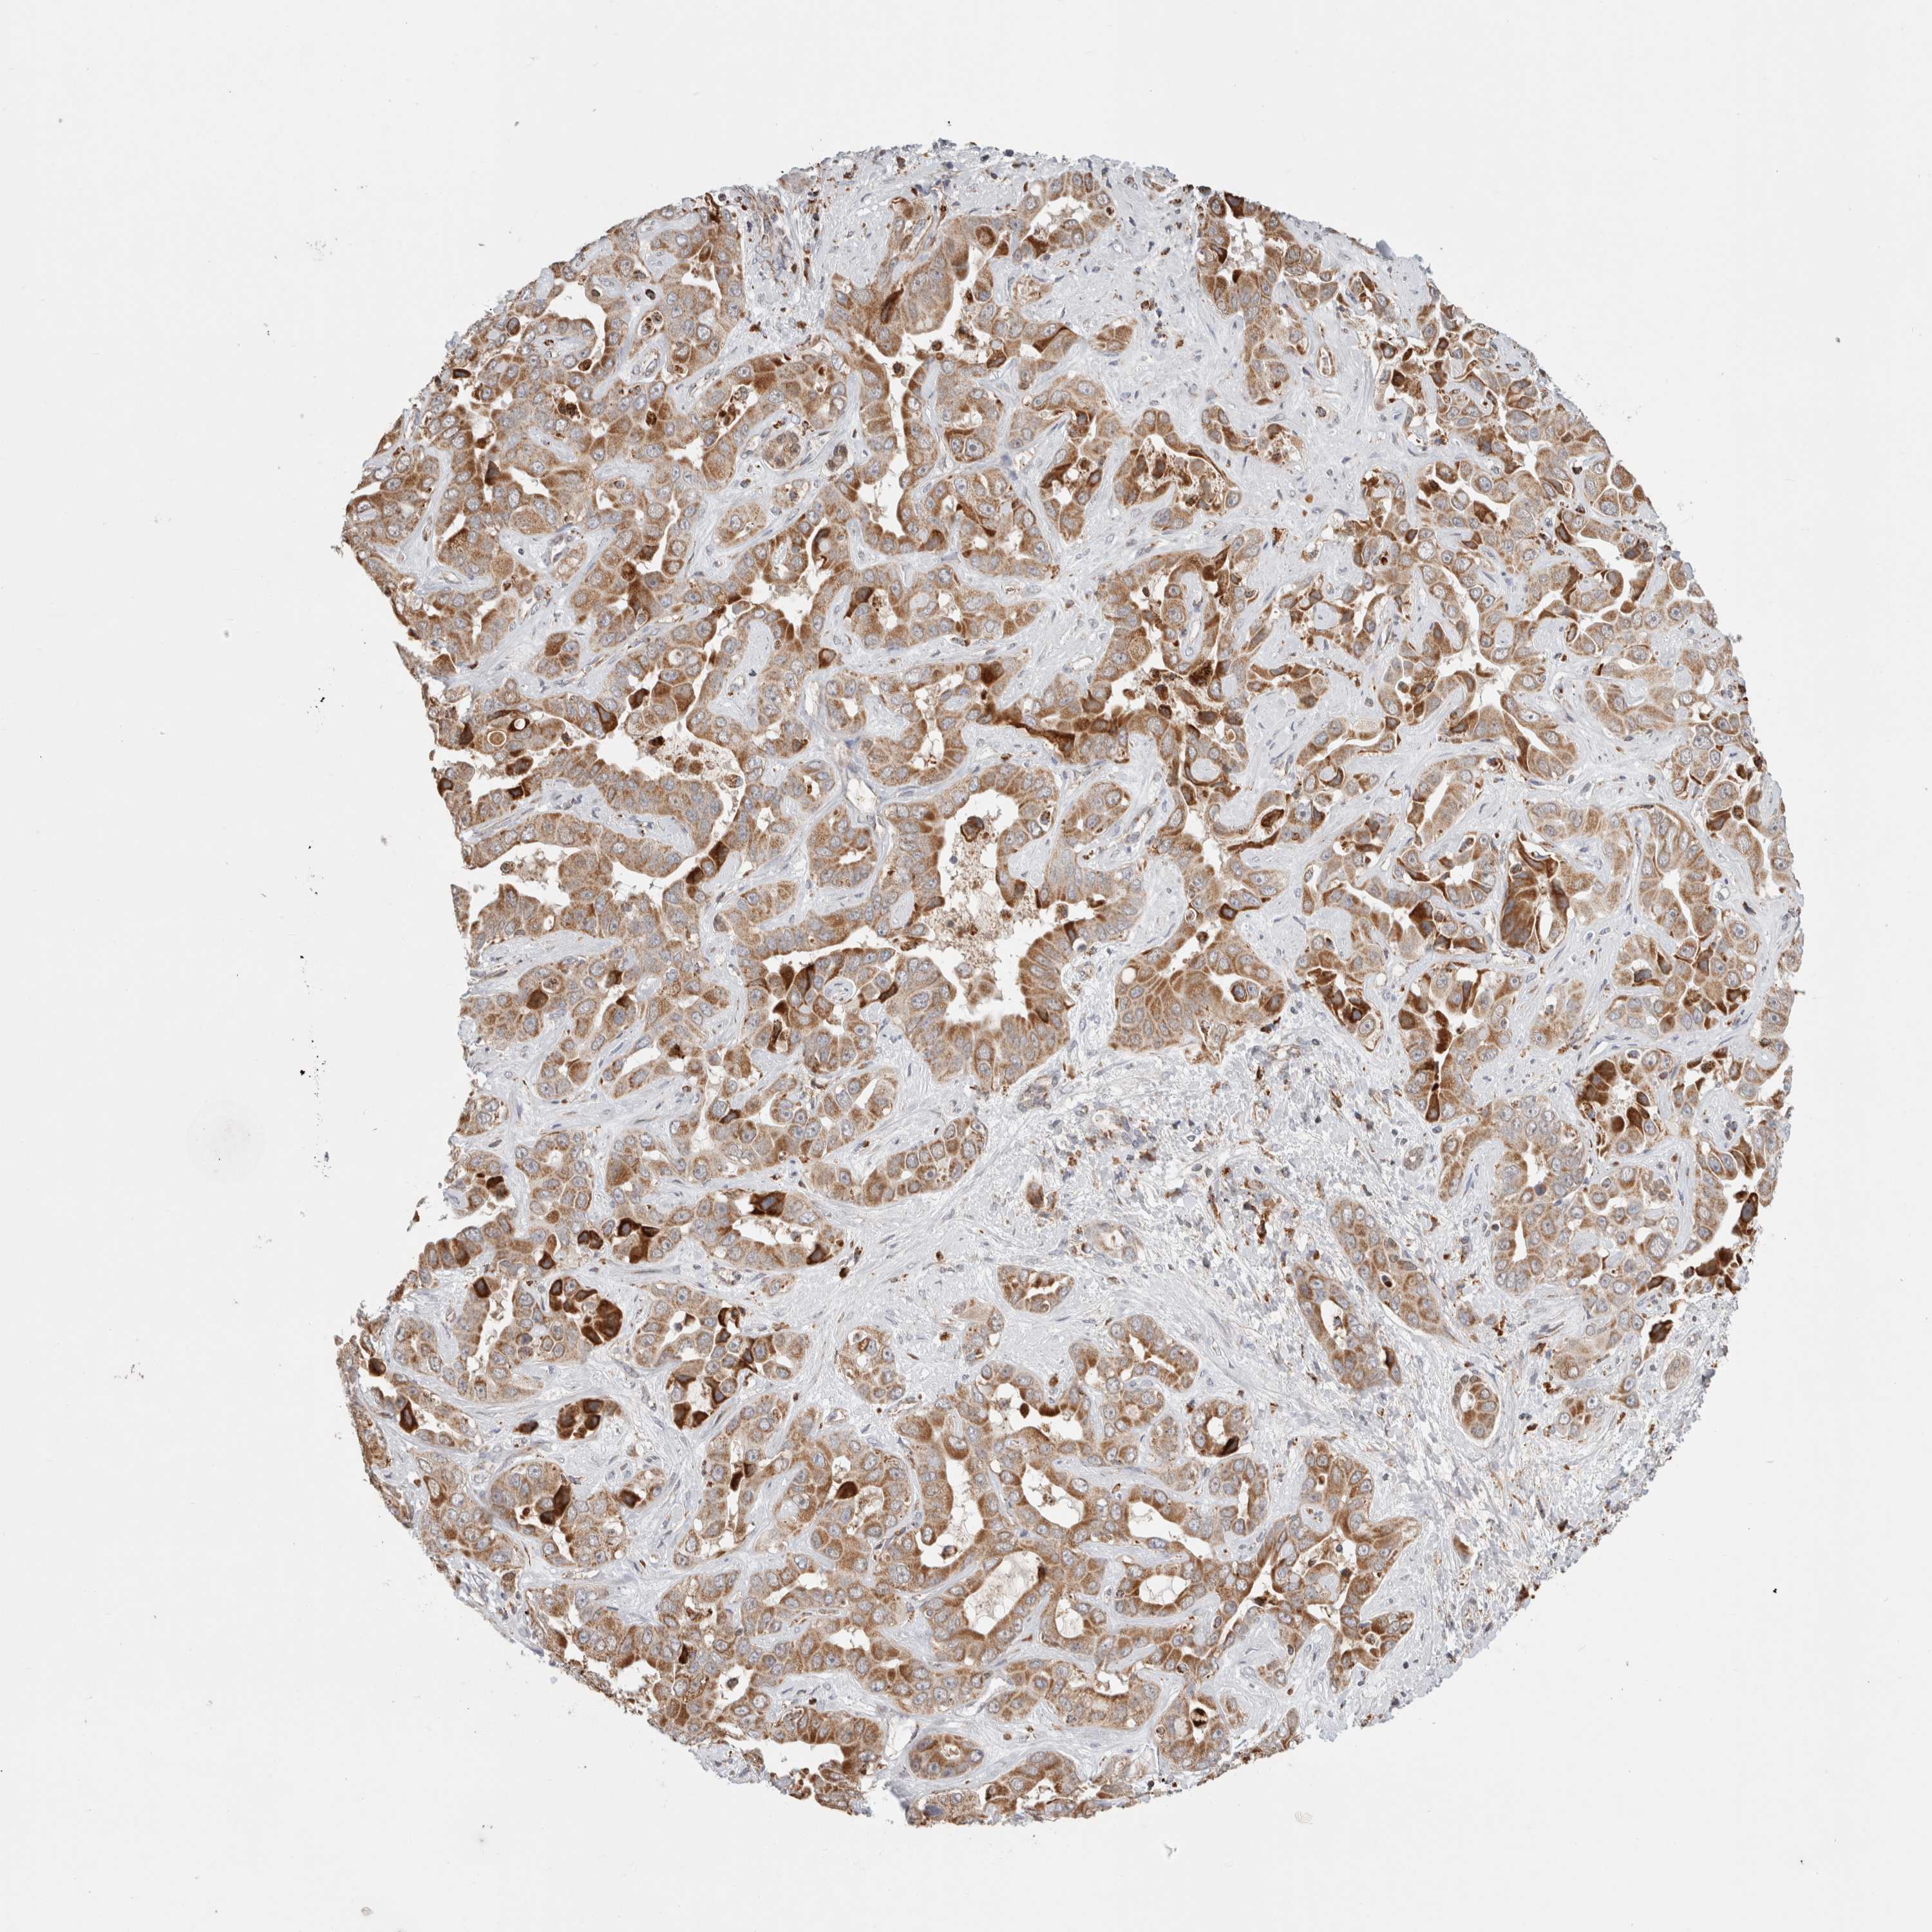

LIVER CANCER - Protein expressioni

A mouse-over function shows sample information and annotation data. Click on an image to view it in a full screen mode. Samples can be filtered based on level of antibody staining by selecting one or several of the following categories: high, medium, low and not detected. The assay and annotation is described here.

Note that samples used for immunohistochemistry by the Human Protein Atlas do not correspond to samples in the TCGA dataset.

Antibody stainingi

Antibody staining in the annotated cell types in the current human tissue is reported as not detected, low, medium, or high, based on conventional immunohistochemistry profiling in selected tissues. This score is based on the combination of the staining intensity and fraction of stained cells.

Each image is clickable and will lead to virtual microscopy that enables deeper exploration of all samples and also displays staining intensity scores, fraction scores and subcellular localization as well as patient and tissue information for each sample.

Antibody HPA023004

Antibody HPA023393

Antibody HPA024430

Staining

High

Medium

Low

Not detected

Intensity

Strong

Moderate

Weak

Negative

Quantity

>75%

75%-25%

<25%

None

Location

Nuclear

Cytoplasmic/membranous

Cytoplasmic/membranous,nuclear

Cholangiocarcinoma

Carcinoma, Hepatocellular, NOS